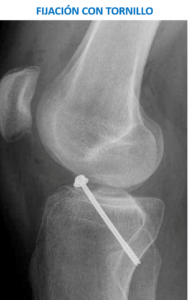

La cirugía suele realizarse con anestesia raquídea (de cintura para abajo) y consiste en limpiar de hematoma la zona de la fractura, colocar de nuevo los fragmentos óseos en su sitio y posteriormente fijarlos con algún dispositivo como suturas especiales, tornillos, etc., que pueden variar dependiendo de las características de la fractura. Ocasionalmente, en casos que la fractura implique un fragmento grande de hueso, se puede necesitar una apertura parcial de la rodilla y colocar un tornillo para fijar la fractura.